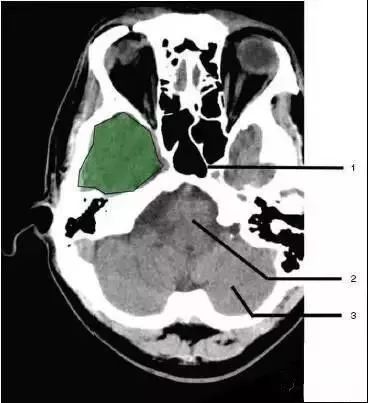

1、蝶窦(Sphenoid sinus)

2、延髓(Medulla oblongata)

3、小脑(cerebellum)绿色部分为颞叶(Temporal Lobe),浅红色部分为额叶(Frontal Lobe)